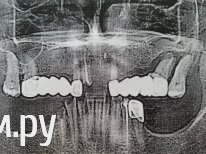

DieBeste Опубликовано 27 ноября, 2013 Поделиться Опубликовано 27 ноября, 2013 Здравствуйте уважаемые специалисты! Размещаю снимок зубов моей родственницы. К сожалению, другими фото не располагаю. Не могли бы Вы, пожалуйста, прокомментировать ситуацию. Буду рада любым отзывам!Женщине 63 года, не курит, сах. диабетом не страдает. Недавно выпали 2 передних зуба. Передние зубы сильно сточены, так как использовались часто для жевания. Глубокий дистальный прикус. Пока располагаю вот такой инфой.Что планируется сделать врачом после первой консультации: - вырвать 5 зубов. Не знаю пока какие. Не могли бы Вы подсказать, есть ли действительно в этом необходимость? Ввиду отсутствия многих зубов жалко как-то потерять еще остальные.- поставить одиночные коронки из керамики. Пациентка попросила из металлокерамики. Вроде бы согласился. Какие все-таки в ее случае лучше: керамика/металлокерамика, одиночные/спаренные?- установить 2 съемных протеза. Есть ли возможность поставить импланты и хотя бы один из протезов посадить на них? Спасибо! Всем удачи! Ссылка на комментарий

IvanK Опубликовано 4 декабря, 2013 Поделиться Опубликовано 4 декабря, 2013 Здравствуйте Мое мнение: удаление 11(?), 22(?), 26,27, 45Далее имплантация или съемные протезы, или комбинация. Выложите более качественный снимок.. Ссылка на комментарий

DieBeste Опубликовано 8 марта, 2014 Автор Поделиться Опубликовано 8 марта, 2014 Здравствуйте всем еще раз! Эпопея с зубами так и не закончилась. Не можем найти врача, так как у всех разное мнение на лечение.Вот что предлагают 2 врача, которые понравились.вч:- стальная коронка на предпоследний зуб справа- на передние зубы - металлокерамический мост- предпоследний зуб слева - удалить (шатается)- простой съемный протез или частично-съемный протез Вопрос:- что делать с поломанным зубом? Можно ли его с помощью штифта нарастить и стоит ли вообще за него браться? Или просто вырвать? нч:- 1 врач: удалить нервы. 2 врач: против, так как, говорит, что зубы не реагируют на горячую/холодную пищу и нервы даже уже умерли. Что делать?- 1 врач: на все зубы стекловолоконные штифты и культевая кобальтовая вкладка, затем металлокерамические коронки (не знаем какие - цельные или по 2-3 или одиночные. После второй консул-и узнаем). 2 врач - никаких штифтов, металлокерамика и на последний зуб справа - вкладка- бюгельные на аттачменах Вопрос: что делать с нервами? Удалять? И нужны ли действительно штифты? И подскажите, пожалуйста, какой метод лечения предложили бы Вы. Прилагаю также новый снимок. Надеюсь, что он более читабельный. Еще беспокоит глубокий дистальный прикус. Не встречались ли в Вашей практике осложнения после исправления глубокого прикуса с помощью протезов/коронок у пожилых людей? Имею ввиду проблемы с нчсуставом (боли и т.д.) Спасибо всем, кто ответит! Ссылка на комментарий